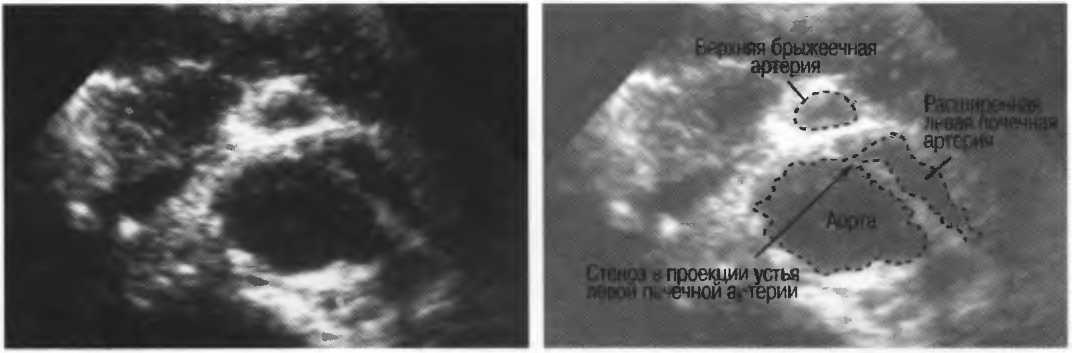

2. Верхняя брыжеечная артерия должна визуализироваться в виде округлого или овального эхонегативного образования, расположенного рядом с поджелудочной железой у здорового взрослого обследуемого (рис. 24). Наиболее простым способом проверки качества изображения является визуализация своей собственной верхней брыжеечной артерии. Сохраняйте эхограммы после каждого исследования для сравнения.

Рис.24. Поперечный срез: верхняя брыжеечная артерия представлена эхонегативным округлым образованием, окруженным эхогенной жировой клетчаткой, расположенным близко к поджелудочной железе.